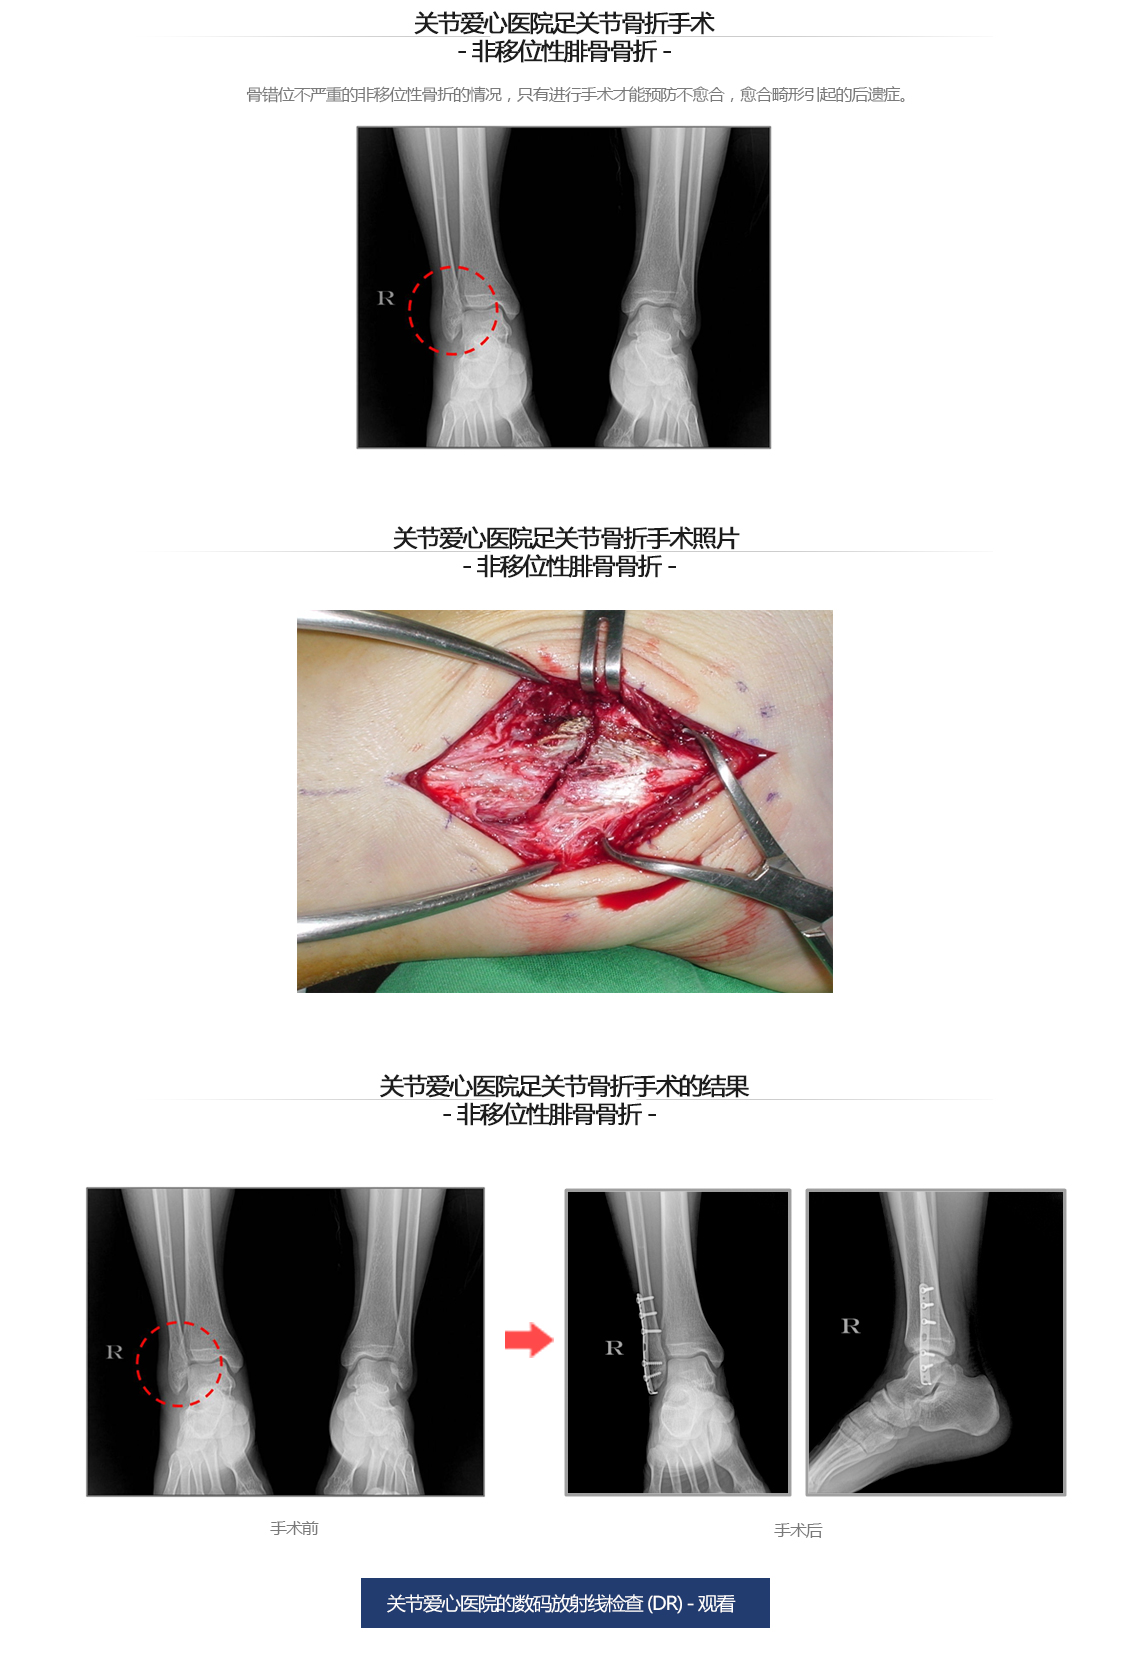

脚腕骨折